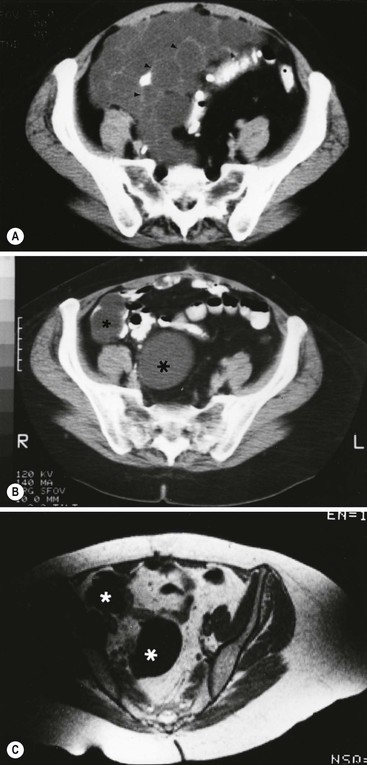

Peritoneal seeding is a common mechanism of metastatic dissemination in advanced gastrointestinal and gynaecological malignancies. Peritoneal carcinomatosis (PC) is the term given to malignant tumour seeding of the peritoneum with most common primaries being the ovarian (71%), gastric (17%) and colorectal (10%) cancers. When cancer cells from a growing primary neoplasm reach the peritoneal surface, they are carried out by the peritoneal fluid and disseminated throughout the peritoneal cavity. Distribution of disease in PC is related to peritoneal fluid circulation along predetermined anatomical routes as previously described in the section ‘Ascites’. This peritoneal fluid circulation and the areas of temporal stasis of fluid explain the distribution of peritoneal seeding. Pooling of ascites favours the deposition and growth of seeded malignant cells. The most common seeding sites include the pouch of Douglas, the distal small-bowel mesentery near the ileocaecal junction, the sigmoid mesocolon, the right paracolic gutter, the pouch of Morison and the right subdiaphragmatic area.3 In general, more aggressive neoplasms exhibit malignant peritoneal deposits closer to the primary tumour, as opposed to less aggressive neoplasms that tend to manifest deposits in remote areas in the abdominal cavity. Variable amounts of ascites may accompany peritoneal seeding but ascites is not always present. Ascitic fluid is sometimes locculated and/or septated, and therefore it may be absent in dependent areas such as the pelvis. Peritoneal deposits (Fig. 30-18) may appear as thickening or enhancement of the peritoneum, nodules or plaques on the peritoneal surfaces, masses or merely stranding of the mesenteric fat.